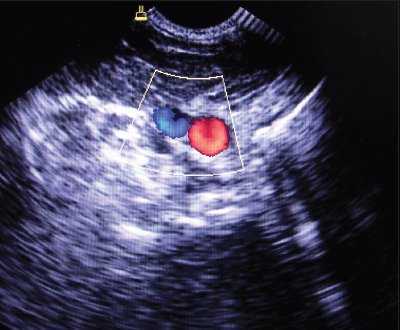

При аномалии размеров отмечалось нормальное расположение внутренней яремной вены и сонной артерии, однако диаметр внутренней яремной вены был меньше диаметра сонной артерии (рис. 4).

Рис. 4. Аномалия размера внутренней яремной вены при ее нормальном расположении (вена меньше сонной артерии и имеет округлый вид).